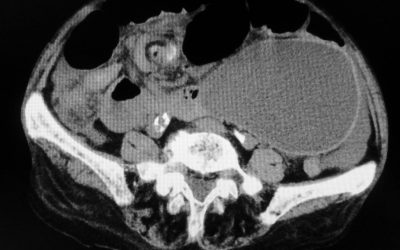

Nodulo intra-pancreatico non metastatico evidenziabile con RMN e 68Ga-DOTA-peptide PET/TC: resezione pancreatica o agobiopsia eco-endoguidata?

di Enrico Ganz l riscontro accidentale di un isolato nodulo intrapancreatico non metastatico nel corso di una tomografia computerizzata (TC) pone il problema di comprendere se sia opportuno un trattamento chirurgico, un periodico controllo della lesione o...